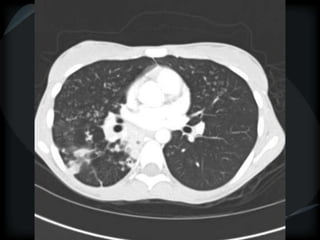

Mosaic CT Patterns

 Vascular obstruction

Airway obstruction

Vascular obstruction

CTPHTN